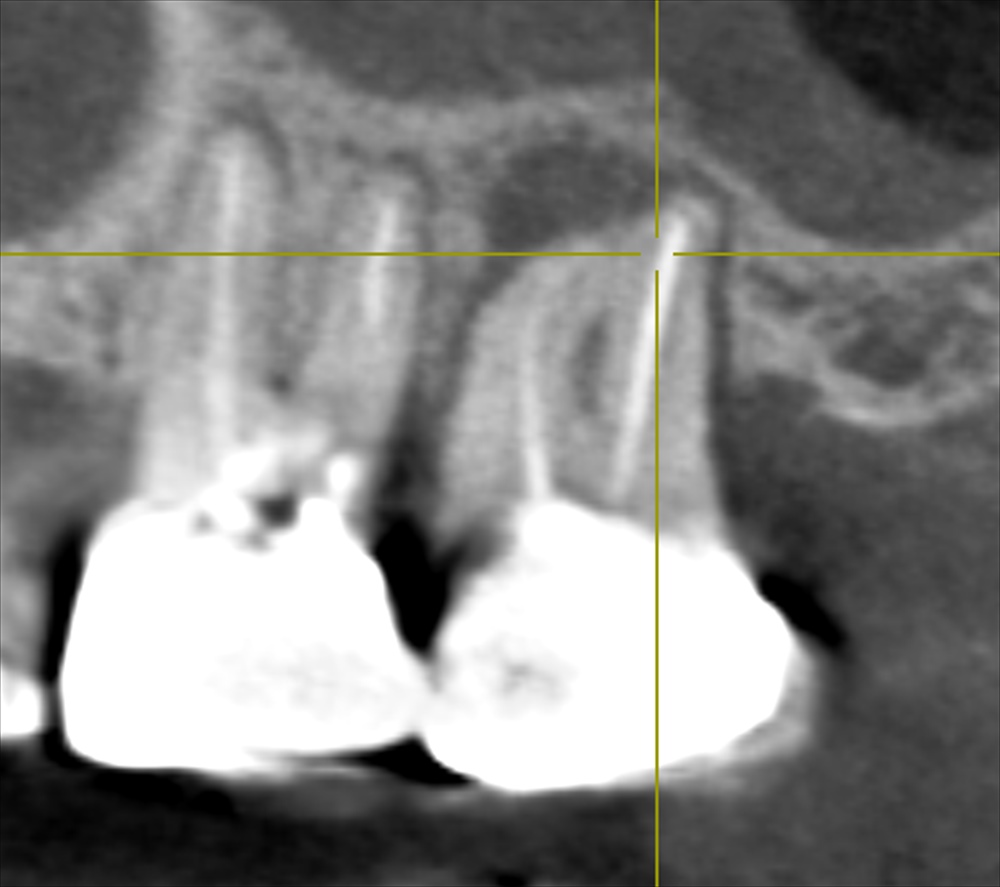

歯科ドック(CT)鼻の部屋にまで広がる重症の虫歯を発見。骨が溶けています。

①根尖性歯周炎

②咬合性外傷(かみ合わせ)

③歯周病

の3つの原因がありました。歯科ドックを行わなければわかりませんでした。このお話を丁寧に患者さまへ説明しご理解いただいた上で治療をスタートいたします。